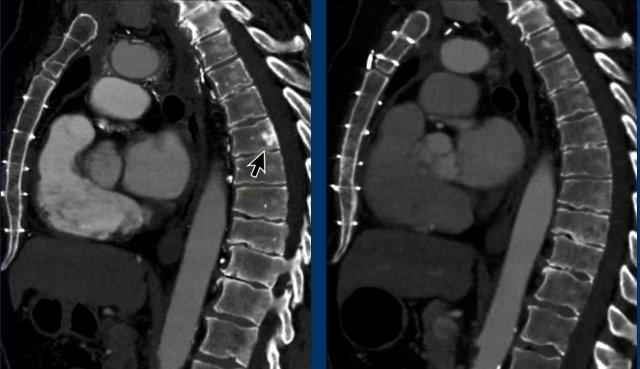

Các hình ảnh này của một bệnh nhân đã được phẫu thuật cắt bỏ thymoma.

Trên phim chụp theo dõi bên trái, phát hiện một tổn thương di căn màng phổi.

Lưu ý rằng nhìn lại, đã có một tổn thương màng phổi rất nhỏ trên phim chụp trước phẫu thuật.

Bài học rút ra là khi nghĩ đến thymoma, cần phải khảo sát màng phổi một cách hết sức tỉ mỉ.

“Bạn chỉ tìm thấy những gì bạn đang tìm kiếm”.